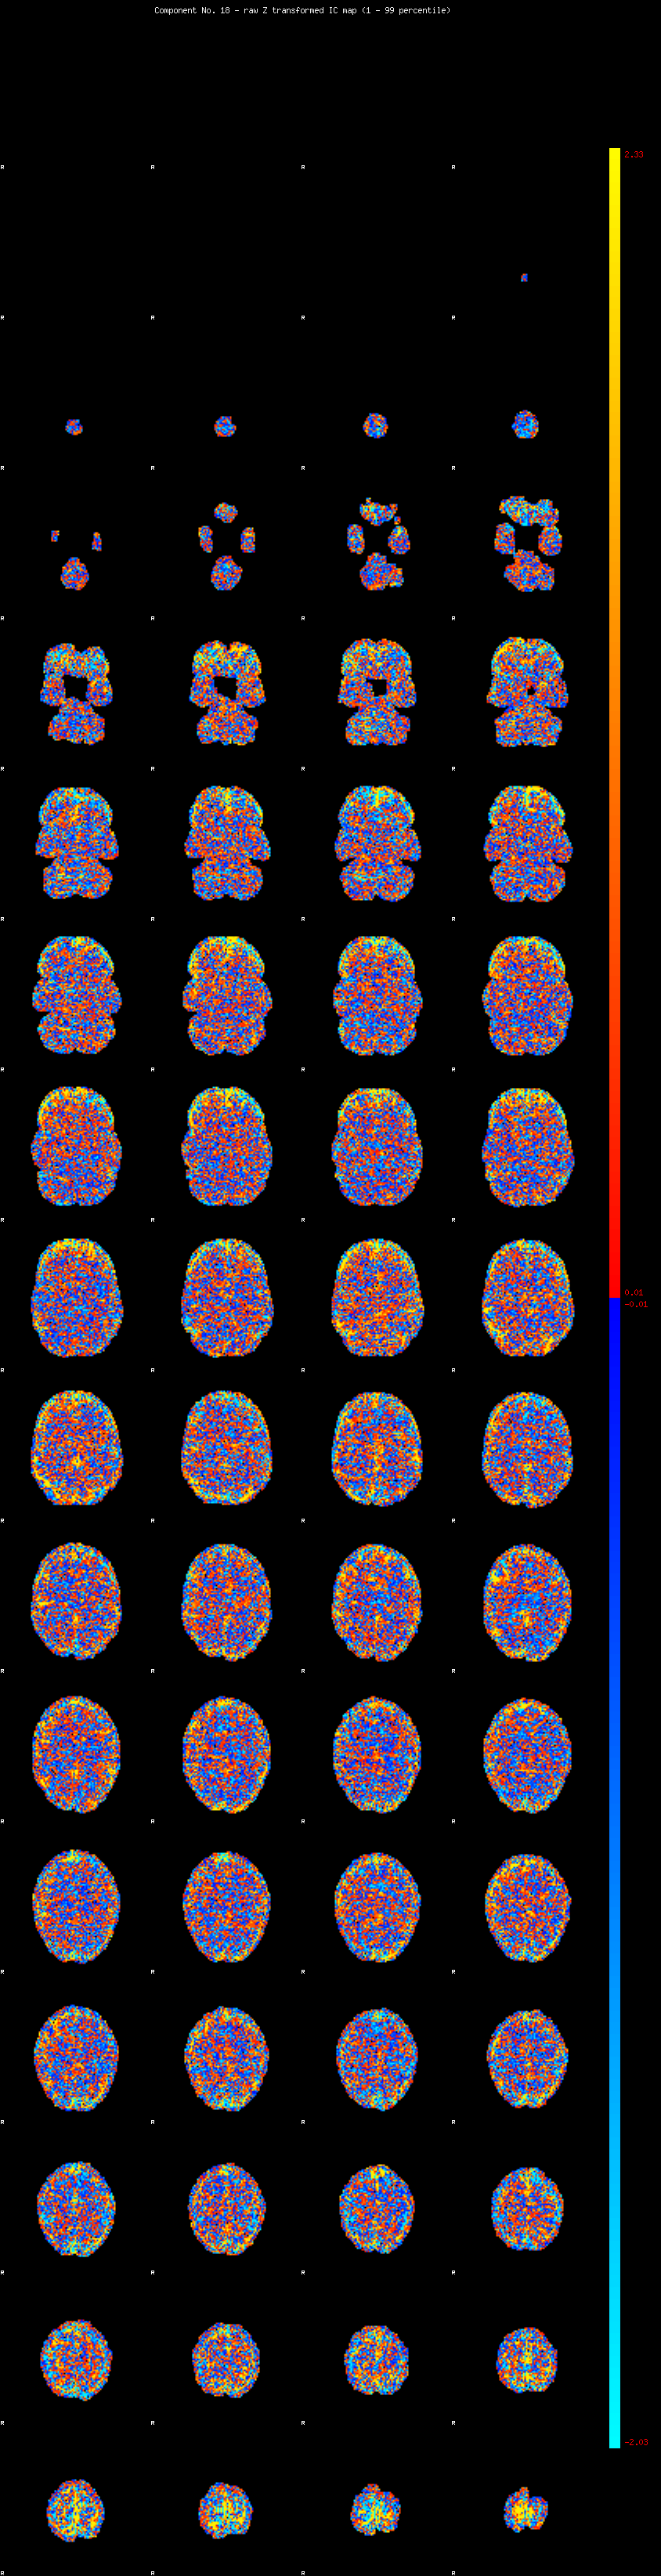

IC_18 Mixture Model fit

Means : -0.000000 2.664149 -2.328556

Vars : 1.000000 2.487326 1.498288

Prop. : 0.896014 0.062055 0.041931